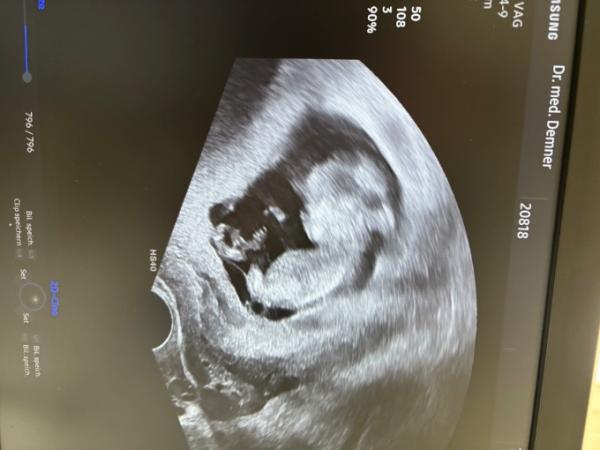

Hallo zusammen Ich hatte gestern einen Ultraschall bei meiner Frauenärztin. Leider ist diese nit gerade sehr kommunikativ auf verschiede Ängste / Fragen von mir . Meinen nächsten Termin habe ich am 11.6. was mich bis dahin verunsichert sind die Schatten im Kopf des Kleinen ( die mir erst zu Hause aufgefallen sind ) und ich bin mir zudem unsicher ob der Abstand den man sieht evtl die Nackenfalte wäre , die ja dann definitiv viel zu groß wäre . Kann mir da jemand helfen ? Vielen lieben Dank für eure Mühe

Bild zu Ultraschall Ssw 12+2 -Auffälligkeiten? - Schwanger - wer noch? Rund um die Schwangerschaft

Ich schließe mich da auch noch mal an, zur Nackenfalte wird auf dem eher unscharfen Bild gar nichts gesagt werden können. Falls du möchtest, mach die Untersuchung dazu. Das wird jetzt vermutlich etwas knapp mit einem Termin für dich, ich fand die ehrlich gesagt total toll, weil man so viel sehen kann und mich hat das sehr beruhigt. Seitdem bin ich deutlich zuversichtlicher. Wenn du einen NIPT Test aber stattdessen zB gemacht hast oder machen möchtest, dann hast du ja vielleicht auch schon etwas für mehr Sicherheit. Alles Gute!

Hi, mach dir keine Sorgen. Sie hätte was gesagt, wenn etwas nicht in Ordnung wäre. Und bzgl. der Nackenfalte: für die Messung gibt es ganz genaue Vorgaben wie eine Mindestanzahl an Messungen, Kopf nach hinten ausgestreckt, genaue Perspektive etc. Wenn du sie genauer untersuchen willst, kannst du das Ersttrimesterscreening machen. Wegen diesem Foto würde ich mich nicht verrückt machen, es ist nur für dich als Erinnerung und hat meiner Meinung nach keinen medizinischen Mehrwert.